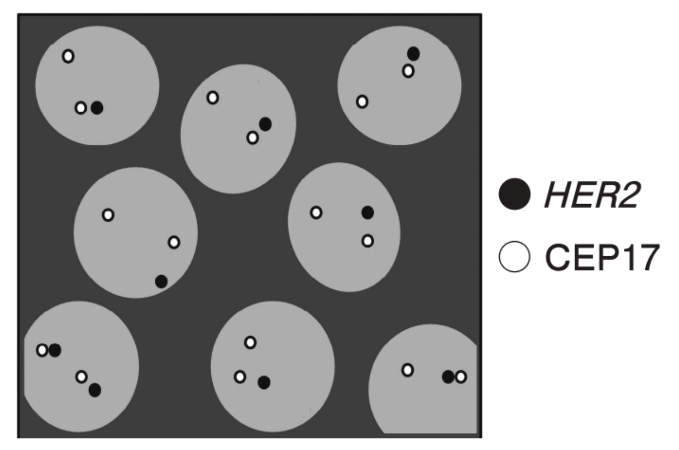

71回 午前 問題51

FISH 法による乳癌HER2検査の模式図(別冊No.10)を示す。

HER2とCEP17のシグナル比(HER2/CEP17)で最も近いのはどれか。

出典:厚生労働省ホームページ 第71回臨床検査技師国家試験の問題および正答について 午前問題別冊

3

【この問題のポイント】

この問題は、乳癌のHER2 FISH(蛍光 in situ ハイブリダイゼーション)検査で使うプローブの読み方を問う問題。

模式図からHER2シグナル(遺伝子座)とCEP17シグナル(17番染色体セントロメア)の数を数え、HER2/CEP17比を求めて最も近い値を選ぶ。

FISH判定では一定数の核でHER2とCEP17を計数し、HER2シグナル総数をCEP17シグナル総数で割って比を算出する。加えて、1細胞あたりのHER2平均コピー数も別指標として算出して判定に用いる運用がある。

3. 3.0

図では、HER2(黒)とCEP17(白)を合計して比を作ると3前後になる。

実際の総数(HER2=49、CEP17=16)を用いると、49/16 = 3.0625 となり、選択肢では3.0が最も近い。